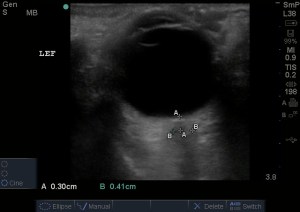

By using the linear high frequency probe with the indicator toward the patient’s right then head, you fan through the eye after placing a tegaderm (to prevent gel discomfort but not necessary) over the closed eye followed by tons of gel. Here is what you will see if normal:

You can see the anterior chamber, ciliary muscle, lens and posterior chamber. The dark hypoechoic linear structure coming off from the back of the orbit is the optic nerve. When it is at its widest on your screen, you measure the diameter 0.3cm from the posterior eye. In adults, any measurement over 0.5cm is considered abnormal and suggestive of increased intracranial pressure. Make sure to the other eye as well and correlate it with your H&P.